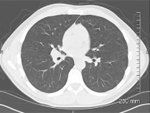

FIGURE 5

CT Scan of the Chest

Follow-up with a noncontrast CT of the chest revealed lobulated hilar masses, bilaterally, with the right greater than left (Figure 5). Small mediastinal lymph nodes are also noted, although no axillary lymphadenopathy is present.